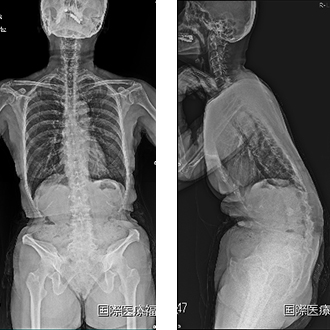

2. 成人脊柱変形に対する変形矯正手術

脊柱変形矯正手術は、脊椎外科の中でも最も難易度の高い手術のひとつとして位置づけられています。当院では脊柱変形疾患における代表的手術である脊柱変形矯正手術に取り組んでいます。近年ではLLIF(5.を参照してください)といわれる固定術が導入され手術が低侵襲化され、80歳代の高齢の方でも条件が合えば手術を選択することが出来るようになりました。

手術によって前傾姿勢が改善して問題なく歩行ができるようになりました。